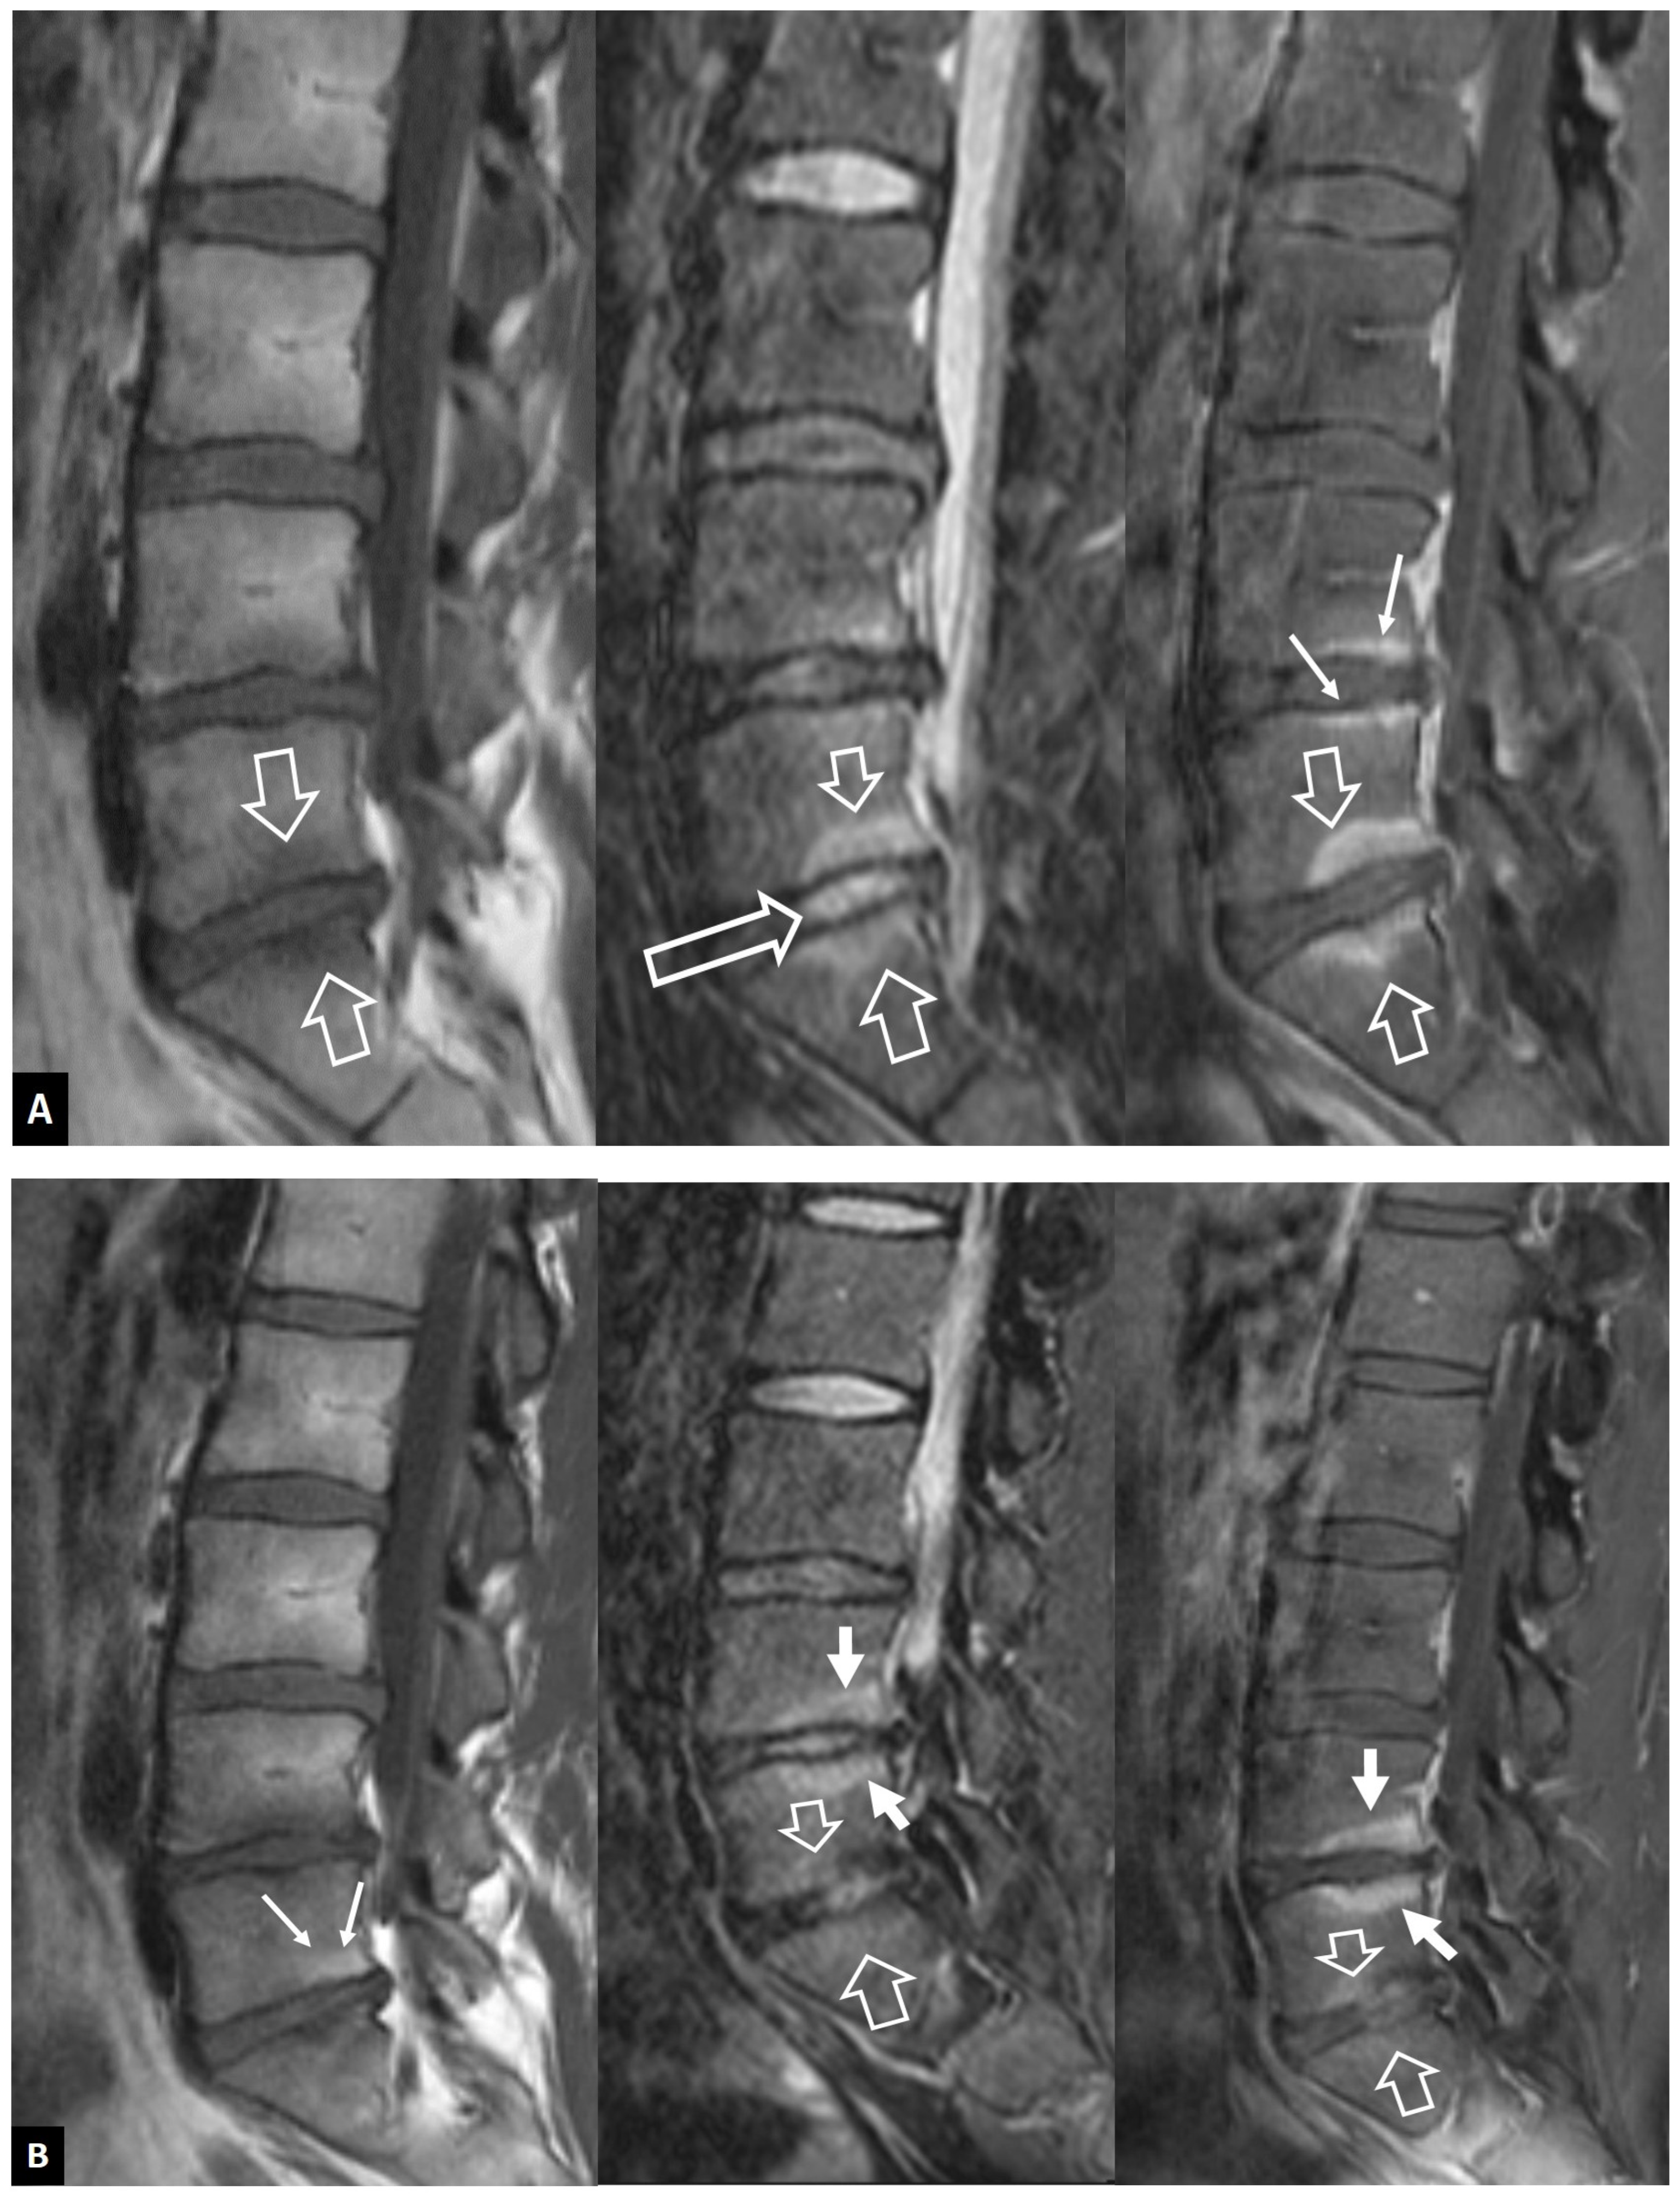

2.1.1. MODIC I Changes

2.1.2. Aseptic Spondylodiscitis

2.1.3. SAPHO Syndrome

2.1.4. Destructive Spondyloarthropathy